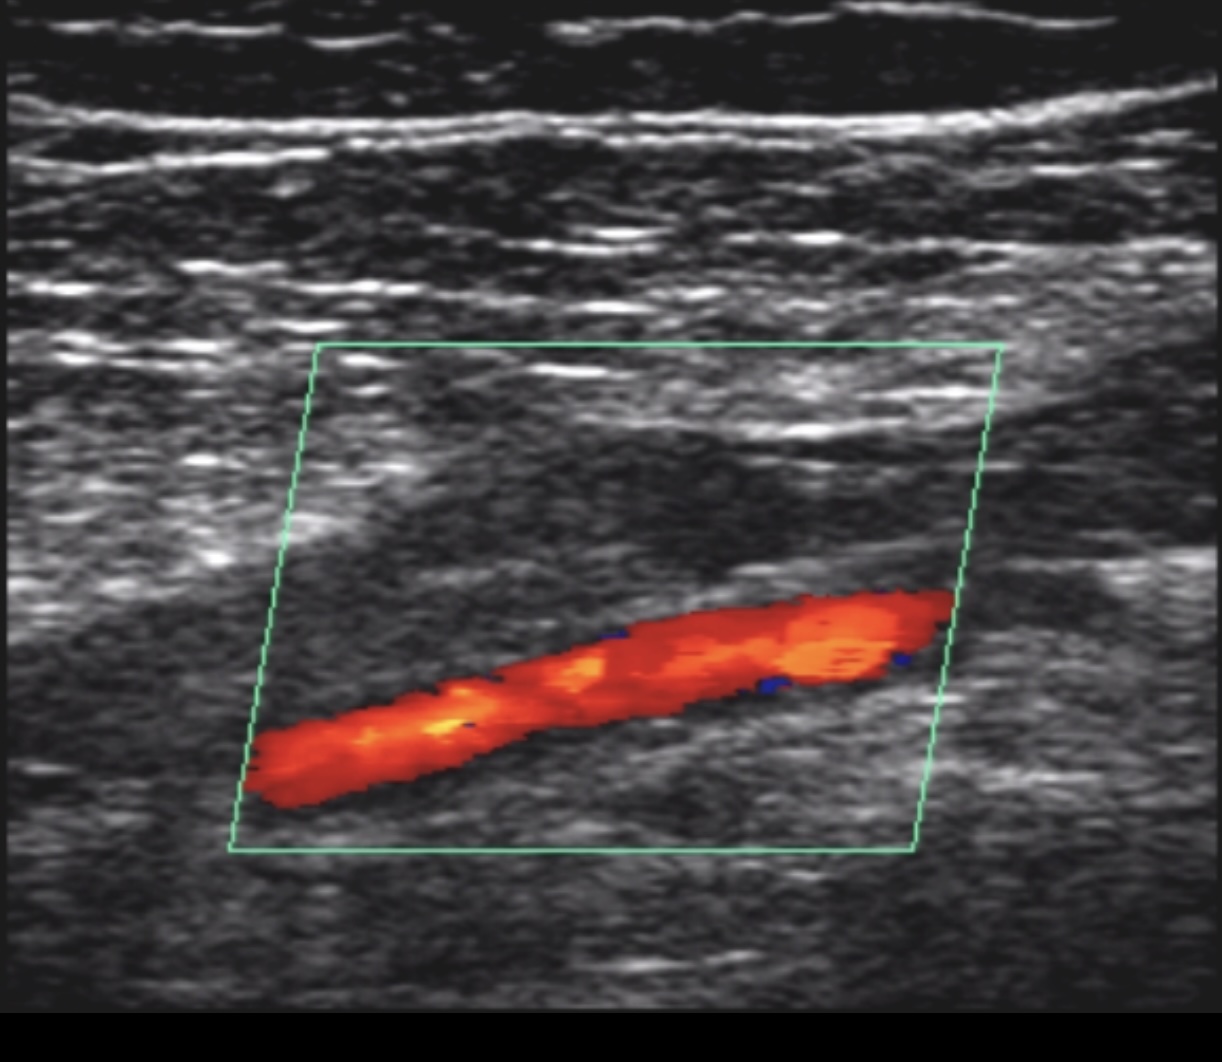

• Ultrasonography

• complete duplex ultrasound

• first-line imaging modality

• non-invasive and inexpensive

• 96% sensitive, 97% specific; operator dependent

• findings

• non-compressible venous segment

• loss of phasic flow with Valsalva maneuver

• increased flow in superficial veins